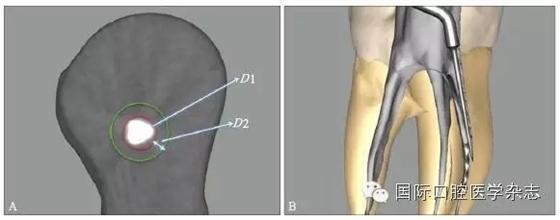

為了盡可能地減少牙本質(zhì)的損失量,應(yīng)當(dāng)根據(jù)分離器械的斷端直徑選擇合適尺寸的超聲工作尖或者環(huán)鉆,然后根據(jù)計(jì)算公式:D≥D1+D2(×2)計(jì)算選擇合適型號(hào)的GG鉆,創(chuàng)造相應(yīng)大小的平臺(tái),為后續(xù)分離器械的取出建立直線(xiàn)通路。其中,D為GG鉆的理論最小直徑,D1為分離器械的末端直徑,D2為超聲工作尖的直徑或環(huán)鉆壁的厚度。當(dāng)超聲工作尖僅在分離器械一側(cè)運(yùn)動(dòng),則公式中D2不需要(×2)(圖6)。具體要點(diǎn)詳見(jiàn)4.1。

A:D1為分離器械的末端直徑,D2為超聲工作尖的直徑或環(huán)鉆壁的厚度;B:當(dāng)超聲工作尖僅在分離器械一側(cè)運(yùn)動(dòng),則公式中D2不需要(×2)。

圖 6 GG鉆理論最小直徑的計(jì)算